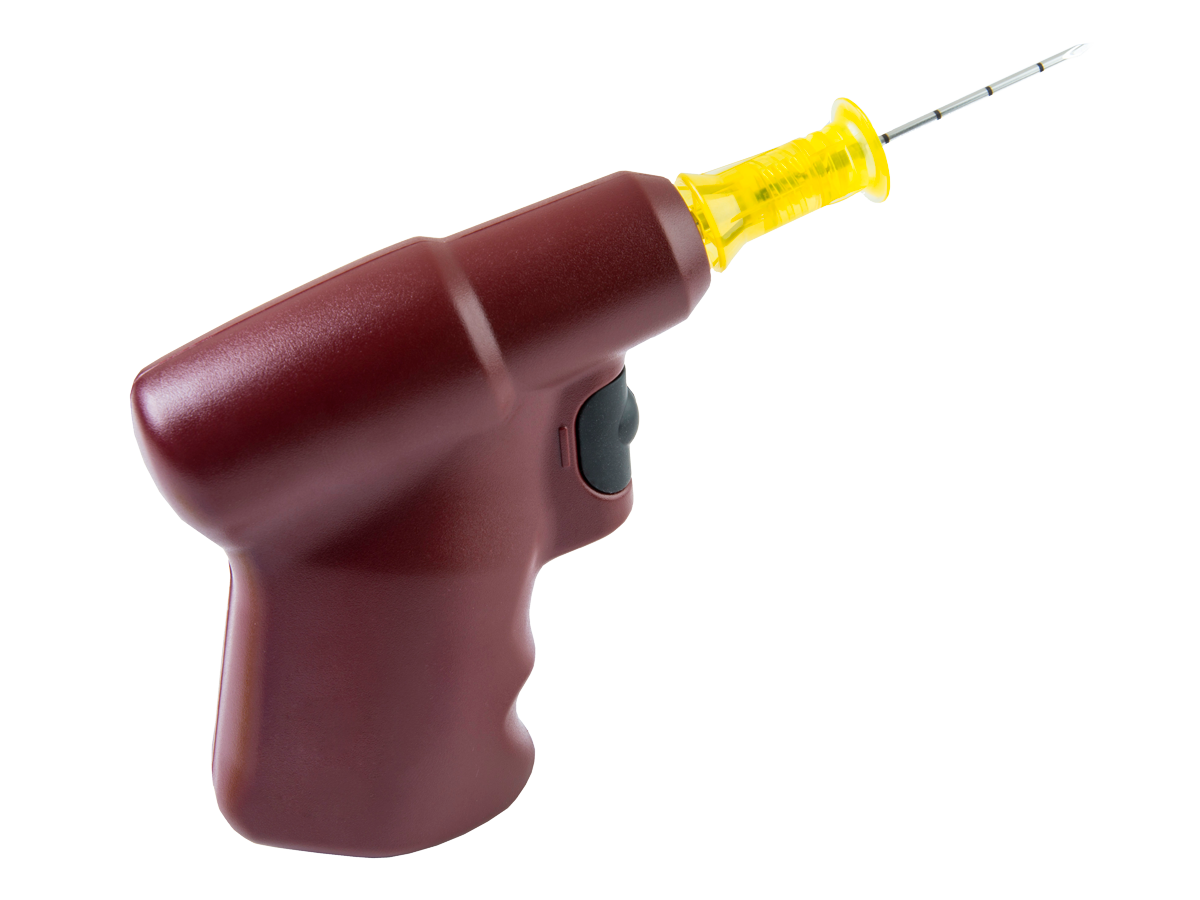

| EZ-IO® Power Driver |